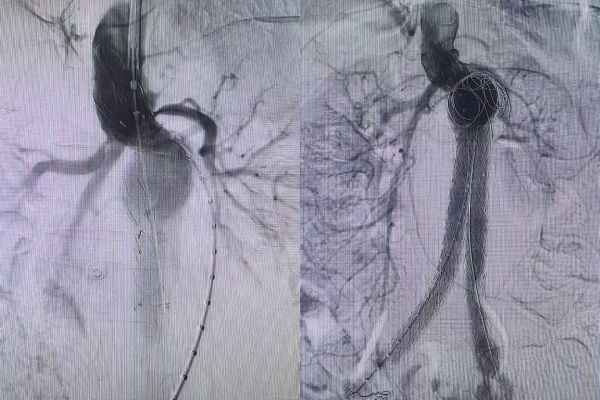

比如剧烈、持续、新发或突然改变的腹部或腰背部疼痛:这是最常见的,也是最关键的警示信号;腹部或腰部剧烈压痛/搏动性包块:患者可能会感到腹部的搏动性包块(瘤体)有明显的压痛,甚至疼痛剧烈到不让触碰;以上典型症状该患者均有着明显的表现。先兆破裂≠小破裂≠稳定状态:是即将发生灾难性大破裂的危险状态。该患者检查后提示:腹主动脉瘤样扩张至正常的三倍,瘤体大小约8cm×13㎝大小。理论上小动脉瘤(直径<5.5cm)且无破裂风险加速证据(生长不快、无症状)可密切监测风险并控制风险因素。大动脉瘤(≥5.5cm)或有症状/增长快/即将破裂,需尽快进行外科修复(开放或腔内手术修复)。该患者瘤体体积,已经远远大于常见动脉瘤体积,也是迄今为止我科室接收的腹主动脉瘤,瘤体体积最大的案例。与此同时患者还出现腹部触痛,肉眼可见的搏动,以及持续性的上腹部疼,血管外科的每一位医护人员都深切地知道,这是一场真正与死神博弈的硬仗。

在血管外科马建仓主任的有力调度下,各专业各司其职,在最短的时间内完成必要的检查以及术前准备工作。虽然时值周末,但是患者的病情刻不容缓,血管外科团队在影像科的协助下顺利为患者实施了介入手术,运用娴熟的技术,为患者成功隔绝瘤体。在手术过程中,由于患者瘤体体积非常大、整体扭曲非常严重、瘤颈短非常严重、极限铆定、重重困难均在扎实的技术前被一一突破,支架置入完成后,通过造影确认完全隔绝无内漏发生。血管外科医护人员用2个小时紧张激烈的奋战,为患者成功排雷,术后24小时即下床活动,行动自如。